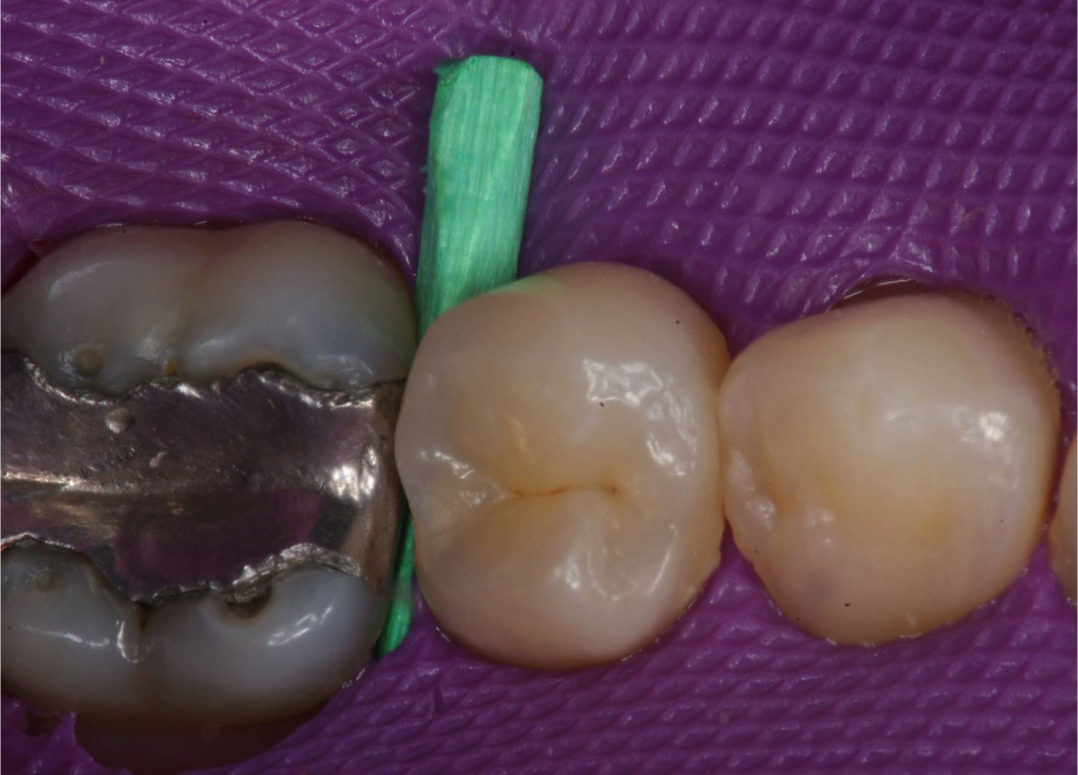

In the case below, a technique for predictable posterior bulk-fill composites is described step by step. For this routine Class II composite resin preparation, caries is apparent radiographically on the distal surface of tooth No. 20 (Figure 7).

The separation is prewedged (Figure 8) to compensate for the thickness of the metal matrix band.

The tooth is prepared.

The sectional matrix of dead-soft stainless steel is placed (Figure 9).

The ring system (V3 Ring [Triodent, www.triodent.com) of the matrix should be straddling the soft-sided wedge to enable optimized adaptation of the gingival margin, which is at greatest risk for recurrent decay (Figure 10 and Figure 11).

A self-etch adhesive is placed on this self-retentive preparation (Figure 12).

The adhesive is light-cured for 10 seconds at right angles to the tooth, as close to the tooth as possible over the Class II proximal box, remembering that the matrix and the ring are moving the light tip slightly farther.

A dual-cure automix composite (HyperFIL) is placed into the proximal box in a single increment of up to 4 mm.

The dual-cure composite—in contrast to light-cure composite—requires only 10 seconds of light-curing for the occlusal section. Complete polymerization will continue with the self-cure component. In this period, the cure reaches a depth of 2 mm to 4 mm and hardens the occlusal surface.

A finishing bur is used on the occlusal surface.

The final restoration polish is completed using diamond-impregnated finishing brushes (Figure 13), which adapt to the anatomic features of the composite.

The result is an anatomic restoration both clinically and radiographically. It is a smooth, esthetic, and well-functioning restoration.

Fig 10 and Fig 11. Wedge and ring used in dead-soft, thin metal matrix.

Figure 10

Figure 11